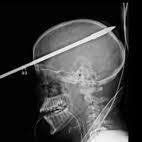

On se souvient du jeune Américain qui avait survécu avec une lance de harpon logée dans son crâne. Au Japon, une adolescente de 15 ans aurait reçu un javelot de 2,6 mètres dans la tête.

Selon les informations de l'Université de Fukuyama Heisi, l'objet aurait été lancé par un autre étudiant. On ignore pour l'instant si le geste était intentionnel ou s’il faisait partie d'un éventuel cours de sport.

Lorsqu'un tel objet se loge dans le crâne, les secours doivent agir très vite. Généralement, ils sectionnent la partie de l'objet qui sort de la tête, puis laissent la pointe dans le crâne, avant de procéder à une intervention chirurgicale, à l'hôpital. Fort heureusement pour elle, ses jours ne sont plus comptés et elle est hors de danger. Sa convalescence devrait durer une quinzaine de jours.